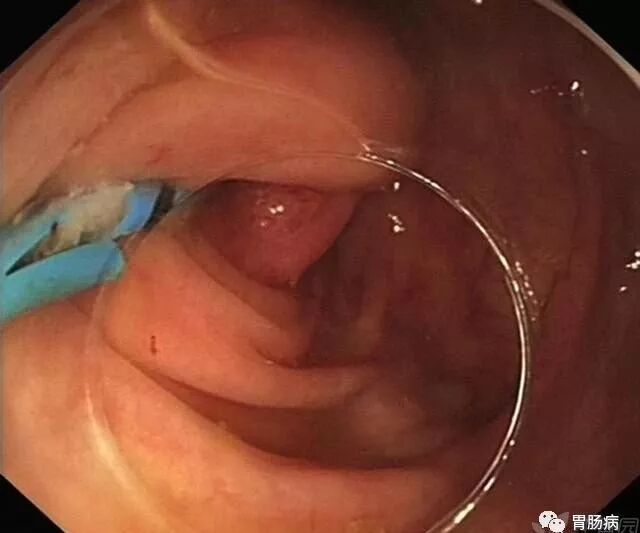

3.球囊或网篮取石术:

通过内镜下置入球囊导管或取石网篮,将粪石取出,原理如ERCP取石术。(黑箭头示取出的粪石)。

4.塑料支架置入及脓液引流:

在充分取出粪石后,置入塑料支架行脓液引流及进一步阑尾腔冲洗(生理盐水+抗生素)。